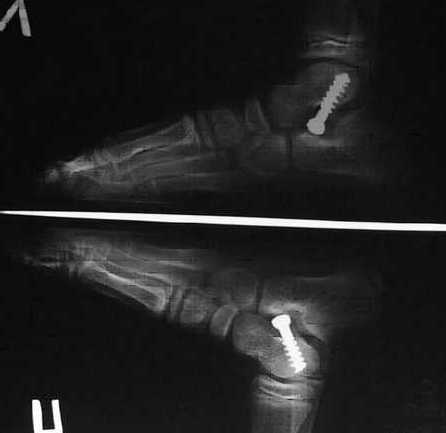

Уважаемый Николай. На счёт артроэрезов у тебя не должно возникнуть проблем. Операции делаются с 80-х годов. Набери в google ?arthroeresis" ?STA-peg ultrahigh-molecular-weight polyethylene(UHMWPE) implant" в разных комбинациях и получишь кучу информации. Кстати STA-peg можно с английского перевести как <затычка> и этим всё сказано. С операцией подтаранный артрориз труднее. Конкретной литературы на английском языке возможно ещё нет. Эту операцию делают в Португалии, Хорватии, Италии и мы. Мы планируем публикацию в каком-нибудь Российском или европейском журнале (ждём средне-отдалённых результатов 1 год), послали тезисы на российскую конференцию <Человек и его здоровье>. У нас молодым аспирантом запланирована кандидатская диссертация, поэтому я не могу выслать подробное описание с картинками, снимками и т.д., если кто-то в СНГ опубликуется раньше нас, то будет, мягко говоря, некрасиво по отношению к моим коллегам (авторство, приоритет, новизна, актуальность и всё-такое :., сам понимаешь). Поговори с руководством, если оплатят проезд, то кто-нибудь из нас приедет, расскажет, покажет, оформим акт внедрения и всем будет польза. Или сам приезжай. Принцип операции: обычный шуруп (6,5 mm под шестигранную отвёртку) вводится минуя пяточную кость под специальным углом (с применением ЭОП) в блок тарана из 8 mm доступа. Это внесуставно блокирует таранно-пяточные вальгус и дивергенцию, а также подсознательно (из-за раздражения рецепторного поля тарзального синуса) заставляет пациента при ходьбе напрягать мышцы формирующие свод. Через 2-3 года (в зависимости от возраста и тяжести) шуруп достаётся. Стопа сформирована и до свидания.

плюс цена 800 евро. В нашем случае шуруп стоит внесуставно и при нормальных взаимоотношениях костей заднего отдела стопы не несёт нагрузки, а, ударяясь о передний отросток пяточной кости блокирует патологическую, подчёркиваю тоько патологическую периталарную эверсию при плоскрстопии. В этом коренное отличие и новизна.

Уважаемый Максим,н ам не нужен биодеградируемый винт ни с Ципрофлоксацином ни без, так как он не должен лизироваться через 2 года. Одному пациенту нужно, чтобы имплант стоял 3 года, другому 5, а третьему всю жизнь, это зависит от возраста больного, эластичности капсульно-связочного аппарата, тяжести деформации и т.д. Теперь о модификациях. Все современые операции - модификации ранее существующих. Даже у аппарата Иллизарова были предшественники и прототипы. Постановка шурупа в нашем исполнении блокирует патологическую наружную ротацию и эверсию пяточной кости, т.е. так называемый Ponseti манёвр, что является ключом и сутью мобильной плоско-вальгусной деформации. Ни одна из ныне существующих техник этого не делает. Вот в чём новизна и новая философия

Как же синус не замыкается, если имплант туда "ввинчивается", как же

он там фиксируется, не замыкая синус? Но проблема даже не в этом. В

упомянутой вами статье: "The stop screw technique—A simple and

reliable method in treating

flexible flatfoot in children" Joerg Jerosch Dr.med.Dr.h.c.a,*, Jochem Schunck a

, Hazem Abdel-Aziz b шуруп ставиться в пяточную кость и упирается

головкой в синус, ограничивая гиперпронацию. То есть опять же в СИНУС.

А тарзальный синус - это анатомическое образование, богатое сосудами и

нервными окончаниями. Отсюда боли, т.е. синуситы. Да и механизм

плоскостопия - это не только гиперпронация в подтаранном суставе.

Постановка шурупа в нашем исполнении не затрагивает синус и действует